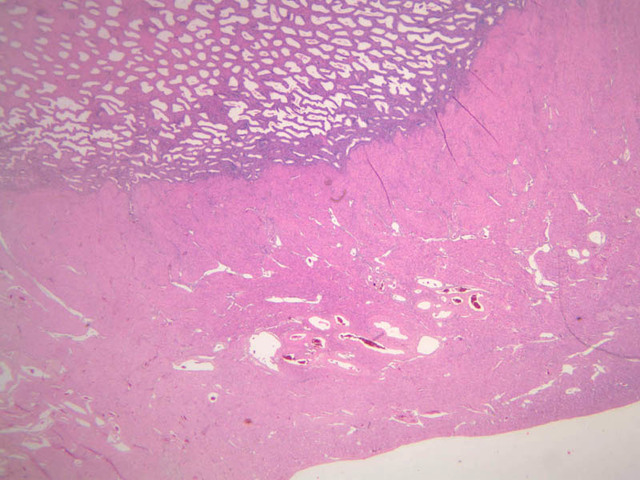

The resting or inactive mammary gland consists of predominantly dense connective tissue with small clusters of ducts and a few glandular elements (slide A-93 [2.5x-labeled, 10x, 20x, 40x] [1x, 2.5x, 10x, 20x]). It is difficult to differentiate between small ducts and alveoli as each is lined by simple low cuboidal cells. Lobes and lobules are not well defined. During puberty, predominantly under the influence of the ovarian hormone estrogen, the glandular or epithelial ducts proliferate and begin to differentiate into clusters of ductal and alveolar units termed terminal ductal lobule units (TDLUs). The non-pregnant gland will form multiple TDLUs that will not fully differentiate until pregnancy-induced growth. TDLUs are classified into Type I, Type II and Type III based on density of the ductules within each lobular unit. Type I and Type II lobules are typical of inactive glands that have not undergone a pregnancy cycle. Type III lobules are seen only in active glands or in inactive glands that have been through a pregnancy. Intralobular connective tissue is loose connective tissue that surrounds the alveoli and ducts within a lobule. The interlobular connective tissue is dense and contains considerable adipose tissue.

During pregnancy, predominantly under the influence of the ovarian hormone progesterone and the pituitary hormone prolactin, the glandular elements proliferate and differentiate to form milk-secreting units. In later stages of pregnancy, alveolar development becomes prominent and the amount of connective tissue and adipose tissue decreases. The secretory cells hypertrophy and accumulate secretory product.

The mammary gland in its active state is a compound tubuloalveolar gland (slide A-92 [10x, 20x, 40x-labeled] [2.5x, 10x, 20x, 40x]; A-94 [2.5x, 10x, 20x, 40x]). At this time, the gland is predominantly glandular tissue. Each alveolus is lined by a simple cuboidal epithelium. At the base of these cells, and within the alveolar basal lamina, are the stellate-shaped myoepithelial cells that are highly contractile and function to facilitate milk ejection.